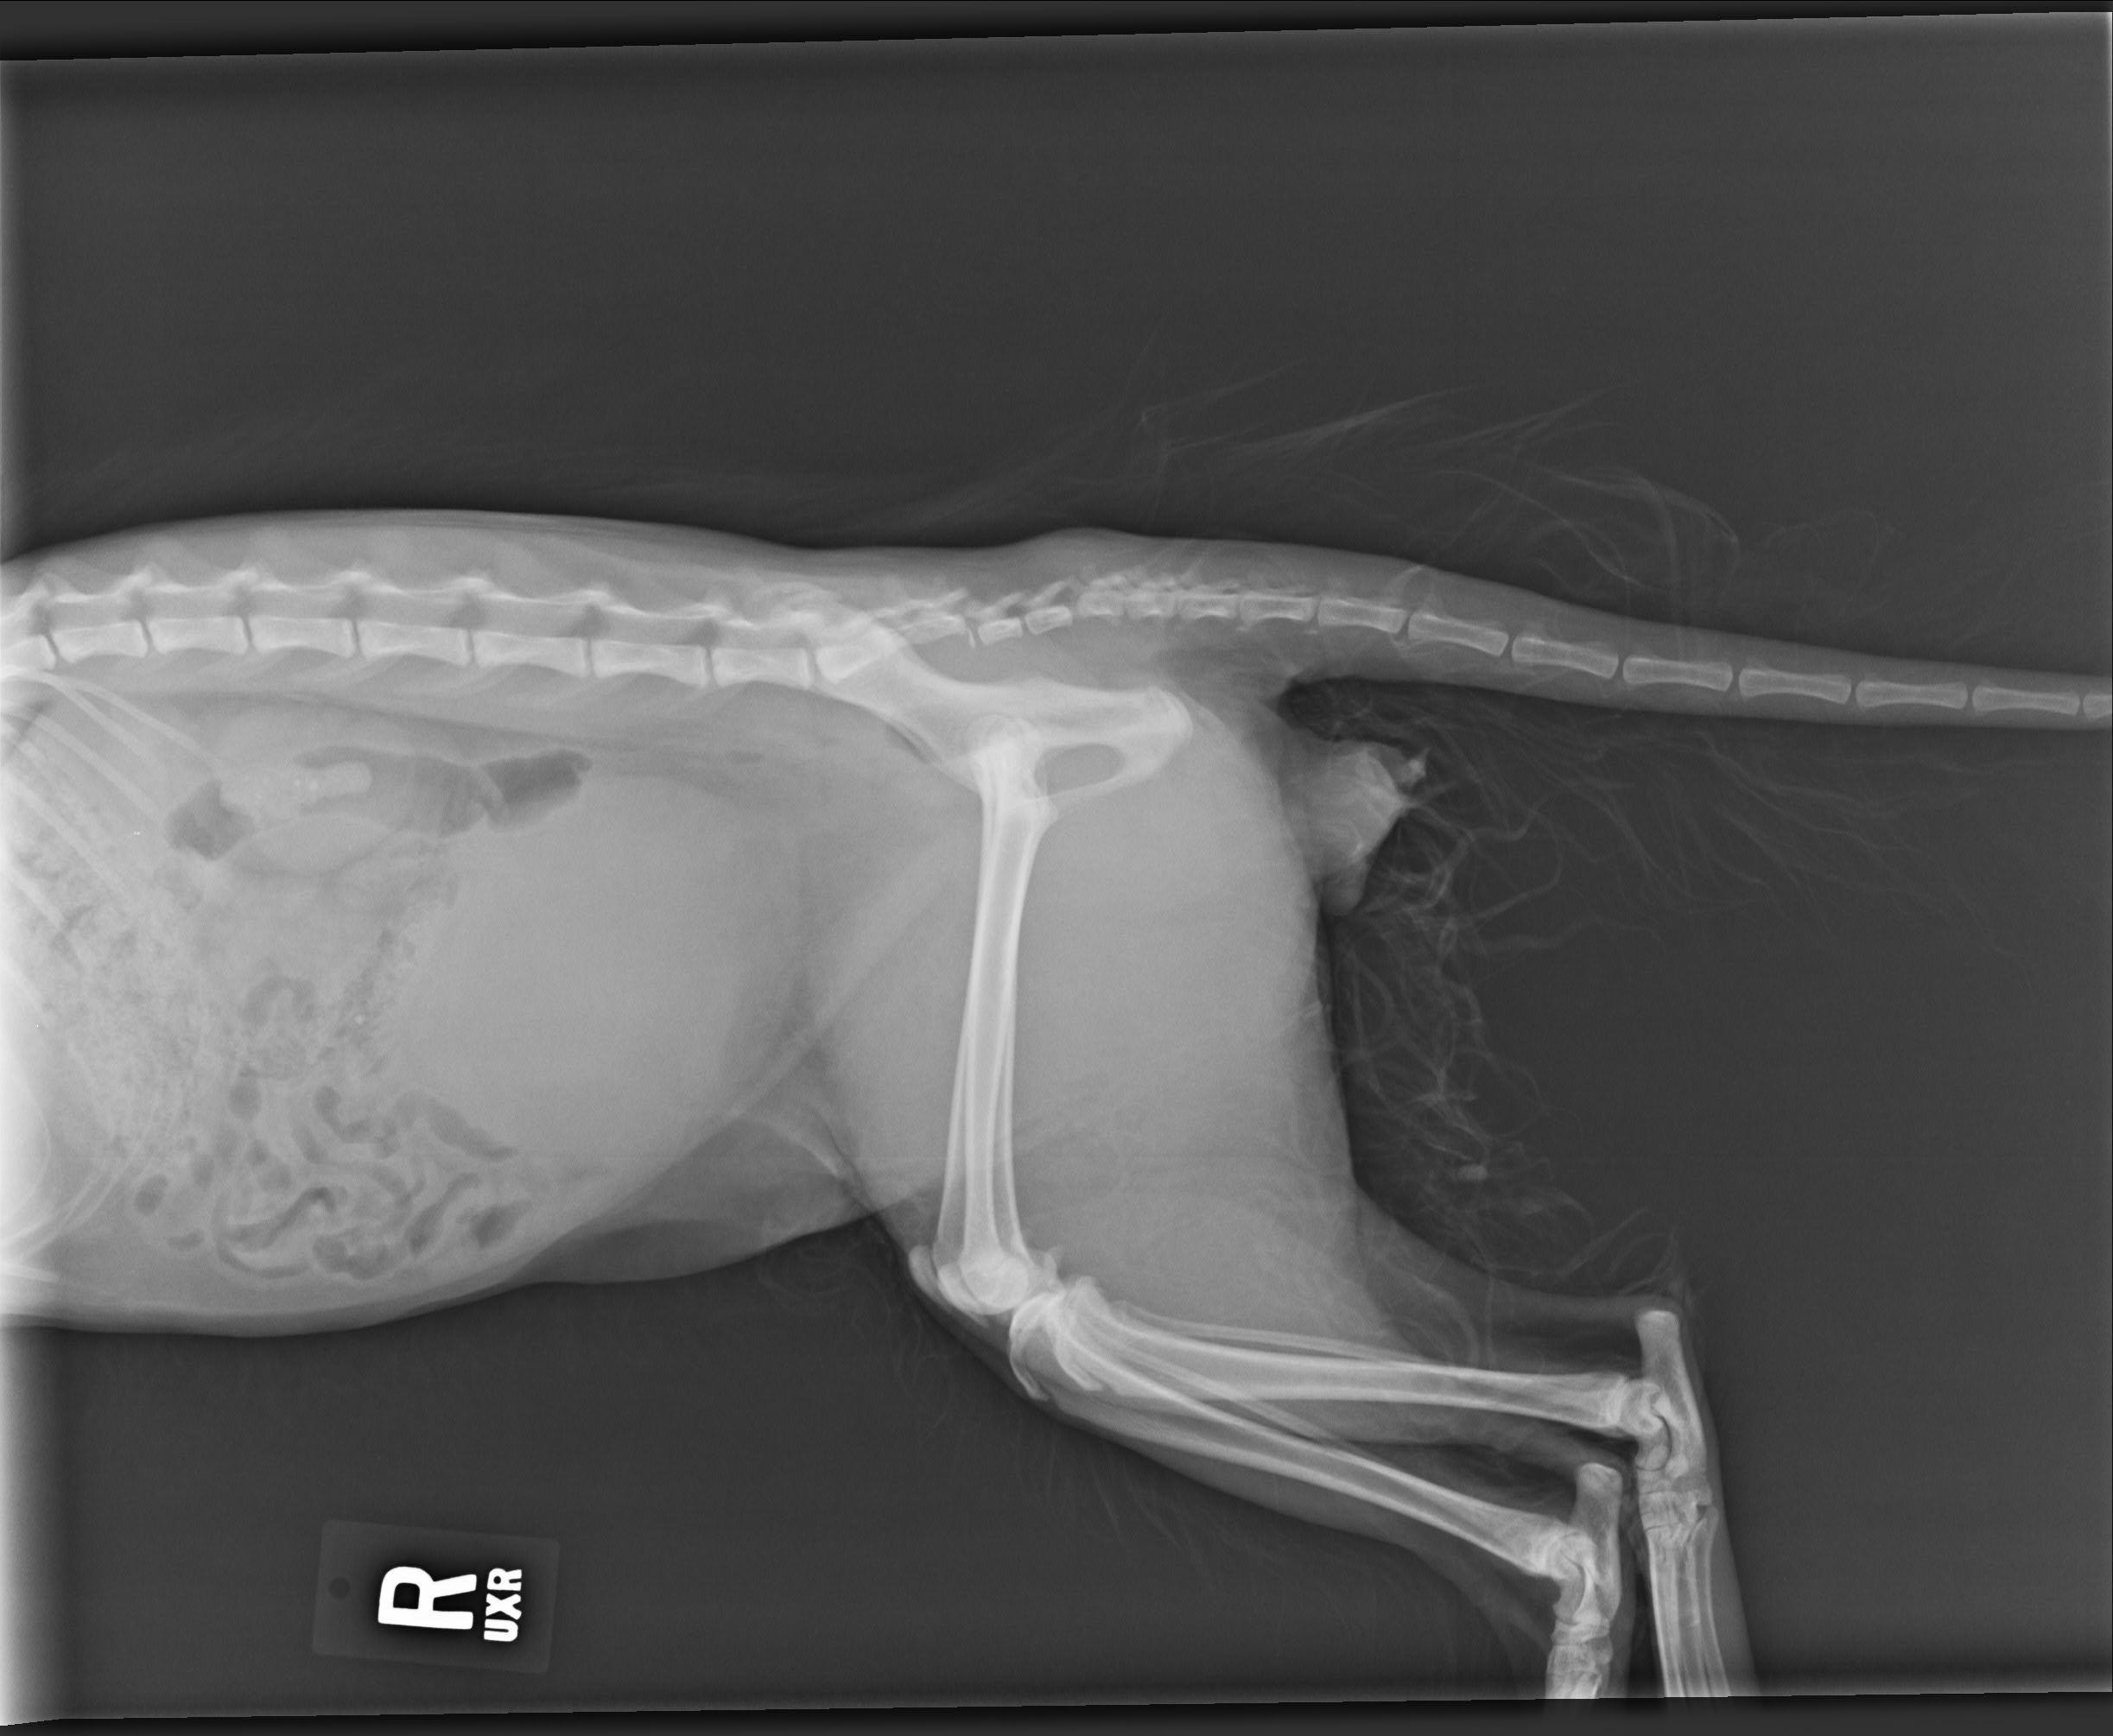

The cat’s spine was fractured in two places and couldn’t lift his tail or urinate on his own. He may have been kicked from behind or kicked while being dangled by his tail, the SPCA says.

An X-ray taken of Skitter B shows his spine fractured in two places., Skitter B, pictured in this contributed photo. Credit: Contributed